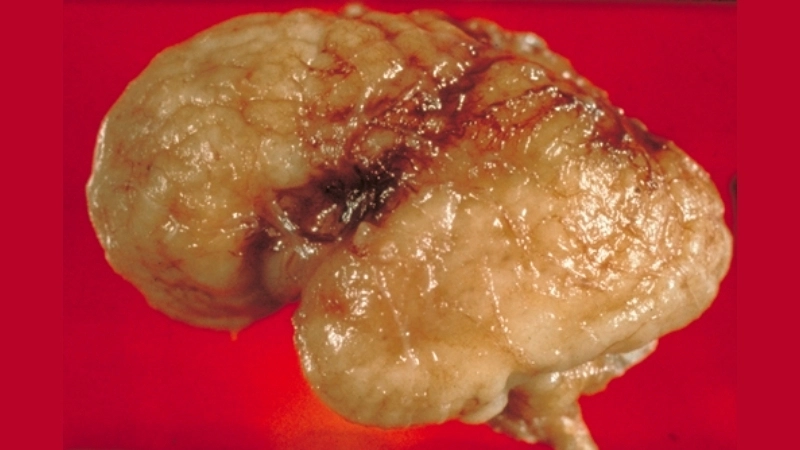

Image description of Viral Encephalitis

Viral encephalitis is a serious condition where a viral infection causes inflammation in the brain. It can range from mild to life-threatening, requiring early detection and treatment.